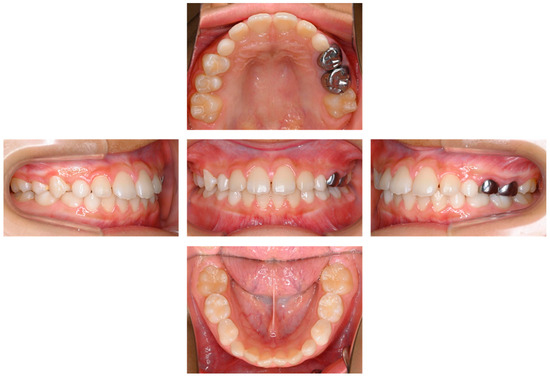

2. Detailed Case Description

| Present case | #55 | Mesio-buccal canal | Reamer | 17 months | Enamel hypoplasia |